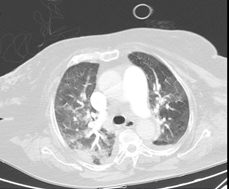

*Pulmonary CT angiography: No signs of PTE. Signs of PHT. Signs of hemodynamic decompensation with probable perihilar cardiogenic edema, bilateral pleural effusion and cardiomegaly (Figures 5 and 6).

Figure 6 No signs of PE.